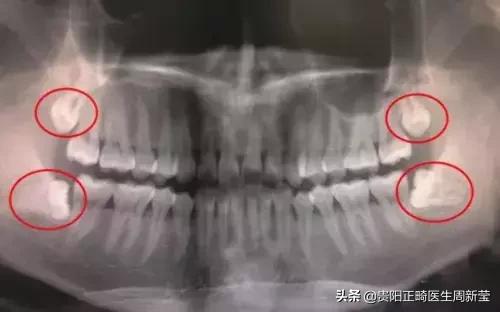

从功能上来讲,第三磨牙属于多余的牙,28颗牙已经可以满足现代人的需求。而且,由于智齿萌出较晚,往往没有足够的位置,智齿很少有能长好的,要么长不出来,要么长得不正。

长不出来,牙龈就会包住智齿,导致牙龈发炎、口腔异味等。

长不正,就是指智齿不能以正常的姿态长出来,它很可能倾斜,把正常的牙齿抵住了导致牙列不齐,甚至导致龋坏。对于长得不好的智齿,可以进行预防性拔除。